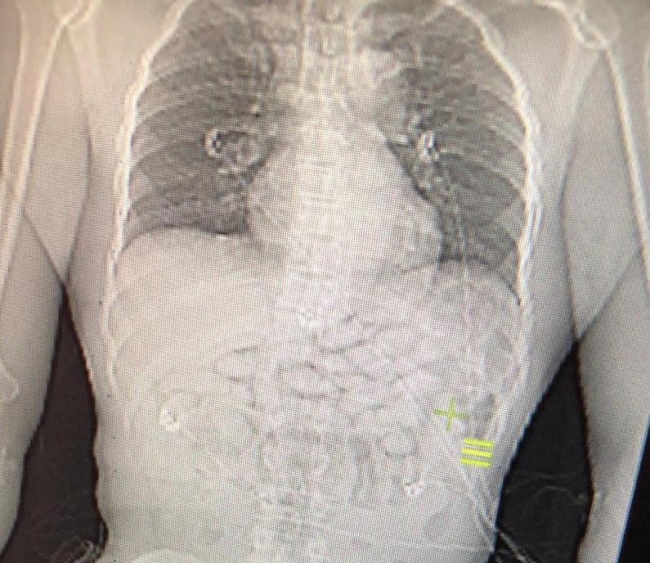

İstanbul Havalimanı'nda, Afrika ülkesi Benin'den aktarmalı olarak Madrid'e uçuşu olan bir yolcunun midesinden 93 kapsül uyuşturucu madde çıktı. Gana uyruklu kişi gözaltına alındı.

29 Aralık'ta yapılan risk analizi çalışmalarında Gana uyruklu kişi, polis ekiplerinin şüphesi üzerine Türkiye'de ilk kez İstanbul Havalimanı'nda kullanılan "yutucu tespit cihazı" ile kontrol edildi.

Cihazda, şüpheli yoğunluk tespit edilmesi üzerine zanlı muayene edilmek üzere hastaneye götürüldü.

Burada yapılan tetkikler ve röntgen kontrollerinde, yolcunun midesinde 93 kapsül içinde uyuşturucu madde tespit edildi.

Gözaltına alınan kişi, tedavisinin ardından işlemleri tamamlanarak adli makamlara sevk edildi.